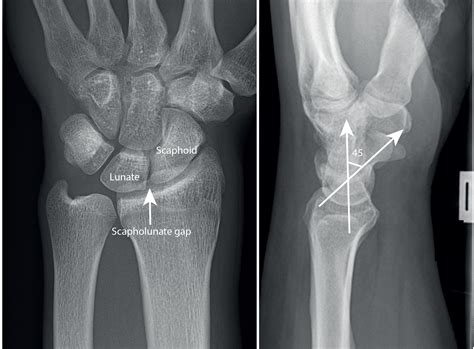

Diagnosing a Scapholunate Ligament Tear involves a combination of physical examination and imaging tests. The diagnostic process typically includes:

• Physical Examination: A healthcare provider will assess the wrist for tenderness, swelling, and range of motion. Specific tests, such as the Watson test, can help identify a scapholunate ligament injury.

• Imaging Tests: X-rays, MRI, and CT scans can provide detailed images of the wrist, helping to confirm the diagnosis and assess the extent of the injury.